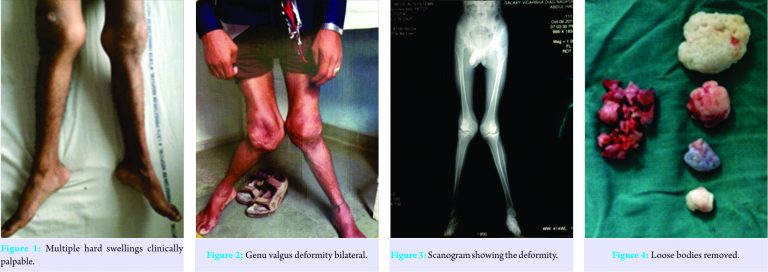

An 18-year-old boy presented with complaints of difficulty in walking with growing deformity with restriction and painful movements of the knee joints bilaterally. The patient gives a history of swelling which was initially there about 8 years back and was accompanied by fever. The patient has taken some treatment for the same by local medics but has not been relieved of his symptoms. Patient’s symptoms are insidious in onset and have gradually progressed in its severity. The patient first noticed swelling over knee right side, which was accompanied by fever and has progressed since then. The patient gives no definitive history regarding any definitive treatment taken for his complaints. On clinical examination, the patient presents with excessive valgus in bilateral foot and knee. The left knee was kept in 15-20° flexion with obvious quadriceps wasting. There was generalized swelling of the knee with fullness in the popliteal fossa. On palpation, effusion was present with normal local temperature. There was tenderness along the lateral joint line. Patella was widened with palpable osteophytes. There was multiple bony hard slightly movable swelling palpated just lateral to the patella, which was extending to the midline beneath the patellar tendon (Fig. 1 and 2).

Irregular hard swellings could be felt along the margins of the medial femoral condyle. During flexion, mobile nodules were palpable over the lateral joint space. Grade II medial laxity was noted in both the knee joint. There was no distal neurovascular deficit. We measured the deformities on standing scanogram (Fig. 3). The right knee was having 30 and the left knee 35° genu valgum. We performed an arthroscopic examination of both knee joints for knowing the status of articular cartilage and to remove the loose bodies (Fig. 4).